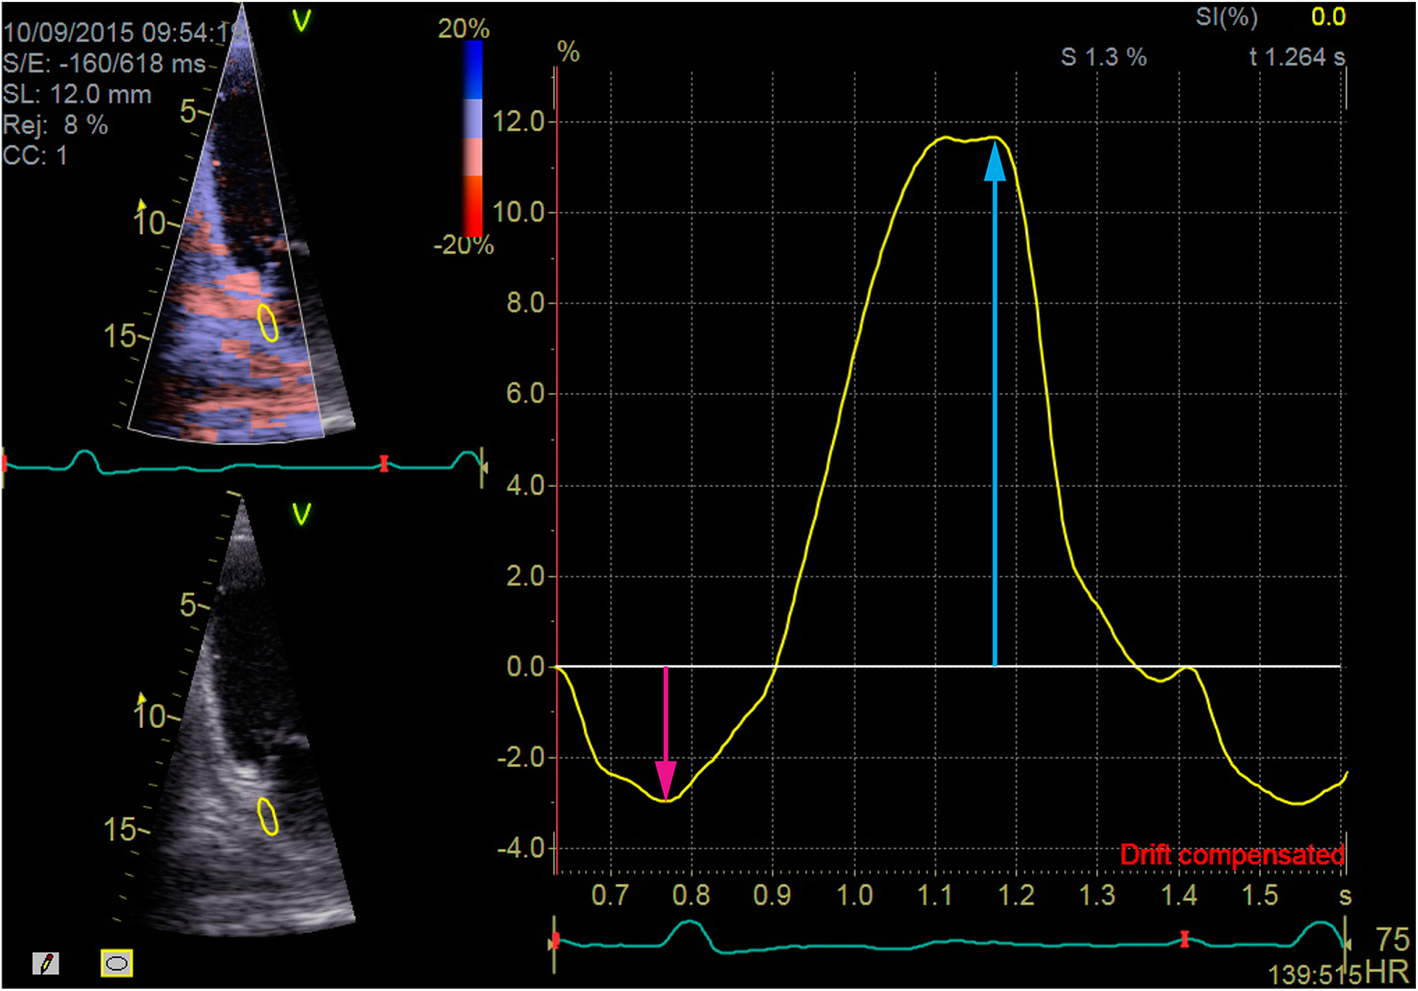

A sample of strain curves Q-analysis in the region of interest. Pink arrow indicates contractile strain (PACS) and blue arrow indicates reservoir strain (PALS) measurements